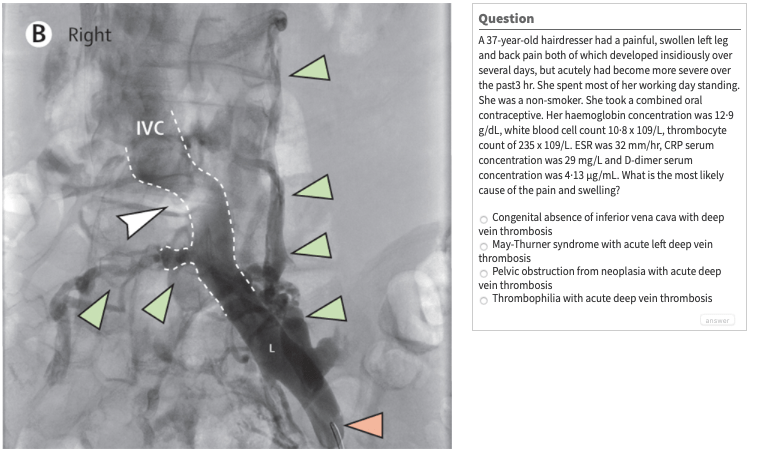

And now it’s time for another episode of The Lancet Picture Quiz!Cue the Jeopardy theme song.“What is….”Click here to answer.#TheLancet #PictureQuiz Share this: Share on X (Opens in new window) X Share on Facebook (Opens in new window) Facebook Like Loading... Published by UBC Abbotsford-Mission Family Practice Residency Program View all posts by UBC Abbotsford-Mission Family Practice Residency Program